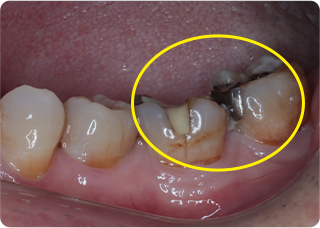

精密根管治療④

術前

術後

| 主訴 | 奥歯で噛むと痛い |

| 治療期間/回数 | 1ヵ月、3回 |

| 価格(税込) | 88,000円(税込) |

| リスク・副作用 | 病変再発、歯根破折の可能性 |

| ポイント | う蝕検知液を用い、むし歯の取り残しが無いようにし、ラバーダム防湿を行い、無菌的に根管治療を行った。根管充填材は、殺菌作用の強い保険適応外のMTAセメントを使用した。 |